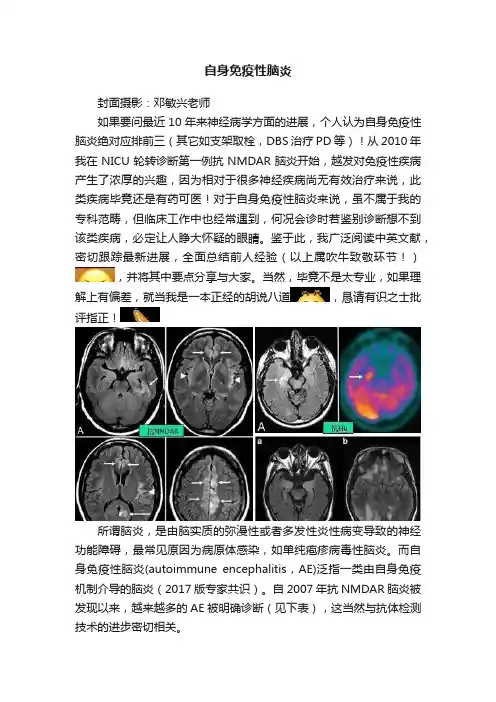

自身免疫性脑炎封面摄影:邓敏兴老师如果要问最近10年来神经病学方面的进展,个人认为自身免疫性脑炎绝对应排前三(其它如支架取栓,DBS治疗PD等)!从2010年我在NICU轮转诊断第一例抗NMDAR脑炎开始,越发对免疫性疾病产生了浓厚的兴趣,因为相对于很多神经疾病尚无有效治疗来说,此类疾病毕竟还是有药可医!对于自身免疫性脑炎来说,虽不属于我的专科范畴,但临床工作中也经常遇到,何况会诊时若鉴别诊断想不到该类疾病,必定让人睁大怀疑的眼睛。

鉴于此,我广泛阅读中英文献,密切跟踪最新进展,全面总结前人经验(以上属吹牛致敬环节!),并将其中要点分享与大家。

当然,毕竟不是太专业,如果理解上有偏差,就当我是一本正经的胡说八道,恳请有识之士批评指正!所谓脑炎,是由脑实质的弥漫性或者多发性炎性病变导致的神经功能障碍,最常见原因为病原体感染,如单纯疱疹病毒性脑炎。

而自身免疫性脑炎(autoimmune encephalitis,AE)泛指一类由自身免疫机制介导的脑炎(2017版专家共识)。

自2007年抗NMDAR脑炎被发现以来,越来越多的AE被明确诊断(见下表),这当然与抗体检测技术的进步密切相关。